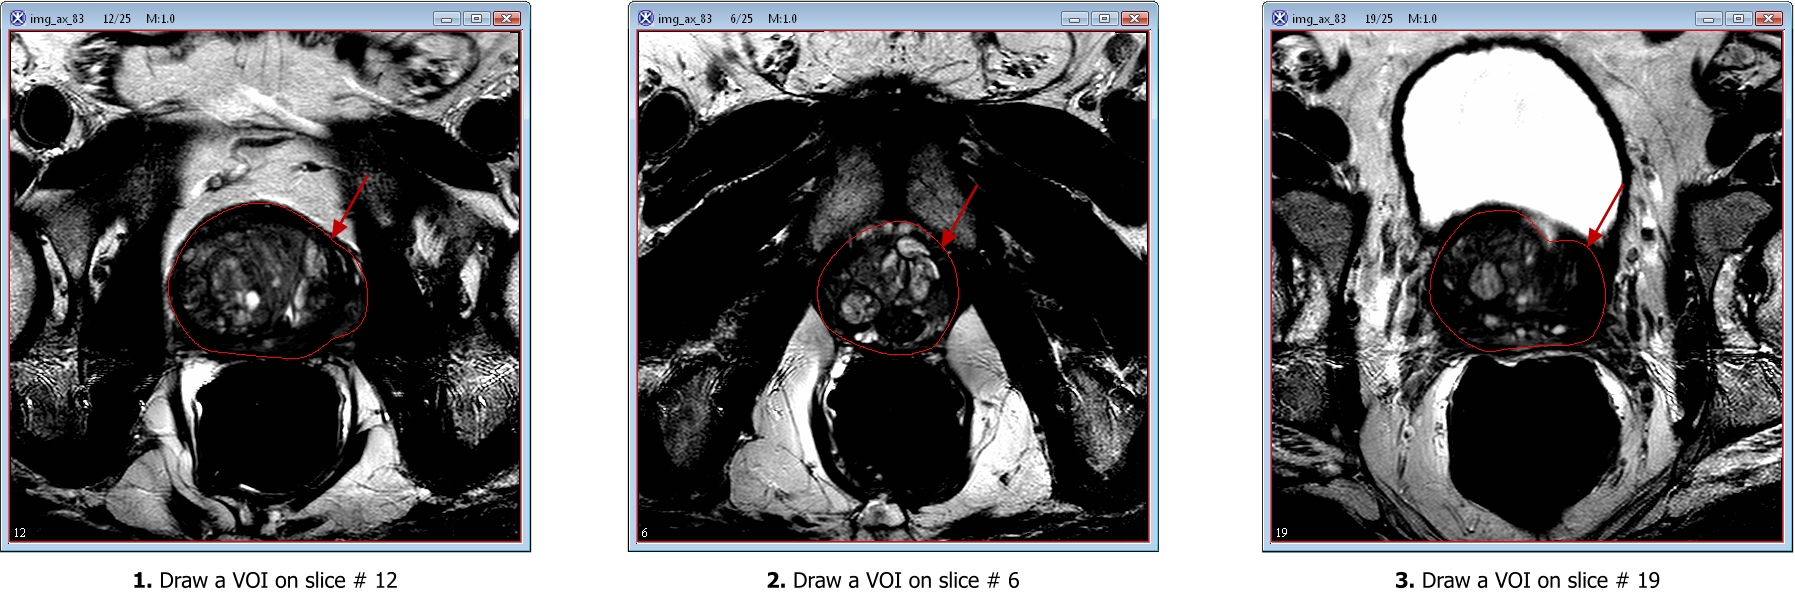

Smoothing VOIs. After delineating VOIs, we need to smooth each VOI. In order to do this, select each VOI and call the Smooth VOI dialog box. The dialog is available from the main MIPAV menu (VOI > Smooth VOI).

In the Smooth VOI dialog box, check the "Replace Original Contour" box, and set "Number of interpolation points" to 100. Click OK. Repeat for all 3 contours.